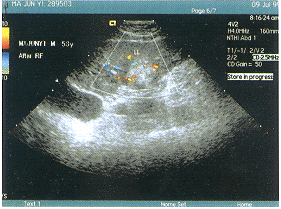

摘 要 目的:利用彩色多普勒显像技术评价肝癌集束电极射频治疗术的早期效果。方法:采用彩色多普勒血流显像仪对28例肝癌患者,集束电极射频治疗术前后1周肿瘤内血流动力学变化进行观察。结果:集束电极射频治疗前28例肝癌患者38个结节中31个可测及血流信号,以动静脉混合血流供血为主,治疗后有血流的31个肿块中11个血流减少,14个完全消失,肿瘤内Ⅱ~Ⅲ级血供及动静脉双重供血明显减少。早期观察认为血流减少或消失与肿块缩小相一致,双重供血的大肿块血流减少不及小肿块。结论:彩色多普勒对肝癌射频治疗前后血流的变化可以给肝癌射频治疗的预后提供重要指标,为重复治疗提供依据。

ABSTRACT Objective:CDFI evaluatescluster electrode radio frequency therapeutic effect of hepatic cancer.Methods:Thehemodynamics changes of 38 tumors in 28 cases of hepatic cancer were investigated by CDFIbefore and after one week of cluster electrode radio frequency ablation.Results:Beforetreatment,the blood signals were found in 31 cancer nodes(79% of all 38 nodes),aftertreatment,blood signals were reduced in 11 nodes and disappeared in 14 nodes.It impliedthat the decrease of blood supply were parallel to the reduction of node size,but the hugenodes with rich blood supply were no better than the small nodes.Conclusion:CDFI is usefulto assess the blood supply in ablation of hepatic cancer using cluster electrode radiofrequency therapy.